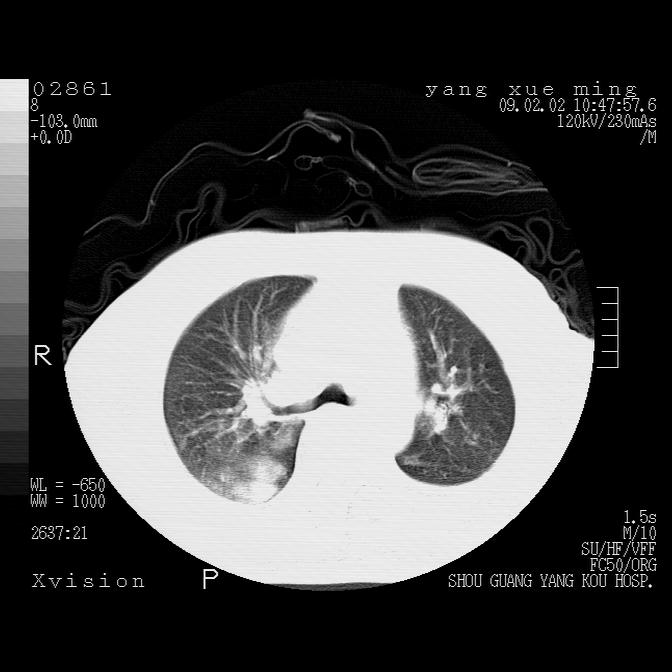

以下是引用zbp537在2009-2-3 19:08:00的发言:[br]我诊断为肺泡性肺水肿。[br]诊断依据:[br]1、心影普遍增大,肺血管增粗,并见絮状高密度影,肺门改变显著。[br]2、临床上表现胸闷咳嗽,无发烧,不是一个典型的肺部感染的病史。

以下是引用lkc8963在2009-2-3 20:11:00的发言:[br]1)右上肺陈旧病灶。2)右下肺团块及团片影,影像表现符合感染。3)左心增大,左冠脉钙化,符合冠心病。4)双侧肺门扩大,以左侧为著,肺动脉干略粗,左上肺局限性气肿,为谨慎起见,需除肿瘤,建议增强。

以下是引用lkc8963在2009-2-3 20:11:00的发言:[br]1)右上肺陈旧病灶.2)右下肺团块及团片影,影像表现符合感染.3)左心增大,左冠脉钙化,符合冠心病.4)双侧肺门扩大以左侧为著,肺动脉干略粗,左上肺局限性气肿,为谨慎起见,需除肿瘤,建议增强.